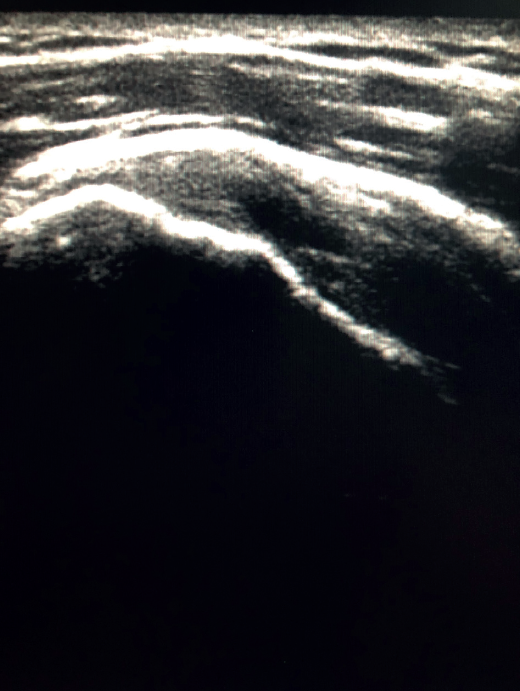

Figure 2. Ultrasound view of the long axis of the tendon of the supraspinatus muscle.

To ensure good ultrasound assessment of the posterosuperior cuff (Figure 2), we instruct the patient to place his or her arm behind the back, with the hand trying to touch the lower vertex of the scapula (Crass position). If the patient is unable to reach or keep this position during the exploration, he or she should be instructed to place the palm of the hand on the ipsilateral anterosuperior iliac crest with the elbow flexed (modification of the Crass position or Middleton position)(25). It is important to explore the tendon to its most anterior margin, as this is a frequent location of symptomatic lesions. For this purpose, in some cases the elbow must be displaced backwards, eliminating the last degrees of internal rotation.